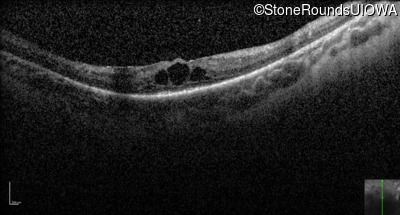

Optical Coherence Tomography - Left - 20/70 +1

Exemplar / OCT Stack